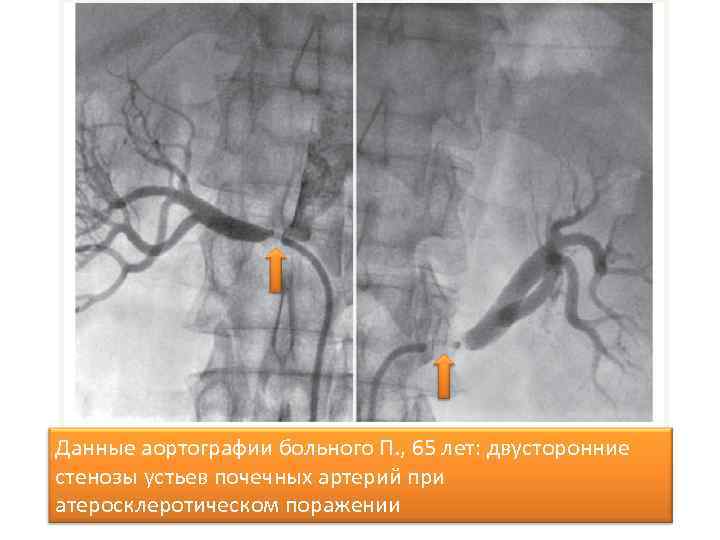

Диагностика вазоренальной АГ • При ультрасонографии и урографии – уменьшение одной почки, замедление выведения контраста. • На УЗИ – эхоскопические признаки асимметрии формы и размеров почек, превышающие 1, 5 см. • Ангиография выявляет концентрическое сужение пораженной почечной артерии. • Дуплексное УЗ-сканирование почечных артерий определяет нарушение магистрального почечного кровотока.

Данные аортографии больного П. , 65 лет: двусторонние стенозы устьев почечных артерий при атеросклеротическом поражении